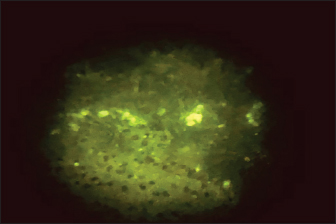

Direct fluorescent antibody technique (DFAT) carried out on brain impression smears from dead mice showed strong positive results represented by apple green spots confirming the presence of rabies (Fig. 2) with 90% positivity (9 out of 10 brain smears diluted up to 1:10,000 within 1–1.5 hours. A negative brain smear showed a negative reaction (Fig. 3) as a dark background. Application of DFAT on BHK-21 cell line inoculated with brain suspensions of infected mice showed intracytoplasmic apple green reactions in nine out of nine (100%) (Fig. 4), while normal cell culture did not show any fluorescent reaction (Fig. 5). This test needs 3–5 days to infect the cells and their preparation for DFAT.

Fig. 2. Positive DFAT carried out on brain impression of experimentally infected dead infected mice showing apple green spots.

Fig. 4. Positive DFAT on RABV-infected BHK-21 cell line showing intracytoplasmic apple green reaction.

The FITC-labeled antibodies to RABV are employed in the direct fluorescent antibody test, which is the gold standard for routine sensitive and specific lyssavirus postmortem identification (Mayes and Rupprecht, 2015). The FA test is also the most popular way to diagnose rabies infection in both humans and animals since it is reliable and results are frequently available within 30 minutes of receiving the specimen (WHO, 2018). In this study, the DFAT carried out on brain impressions of dead experimentally infected mice and infected BHK21 cell lines showed strong positive results with 90% and 100%, respectively, within 1–1.5 hours.